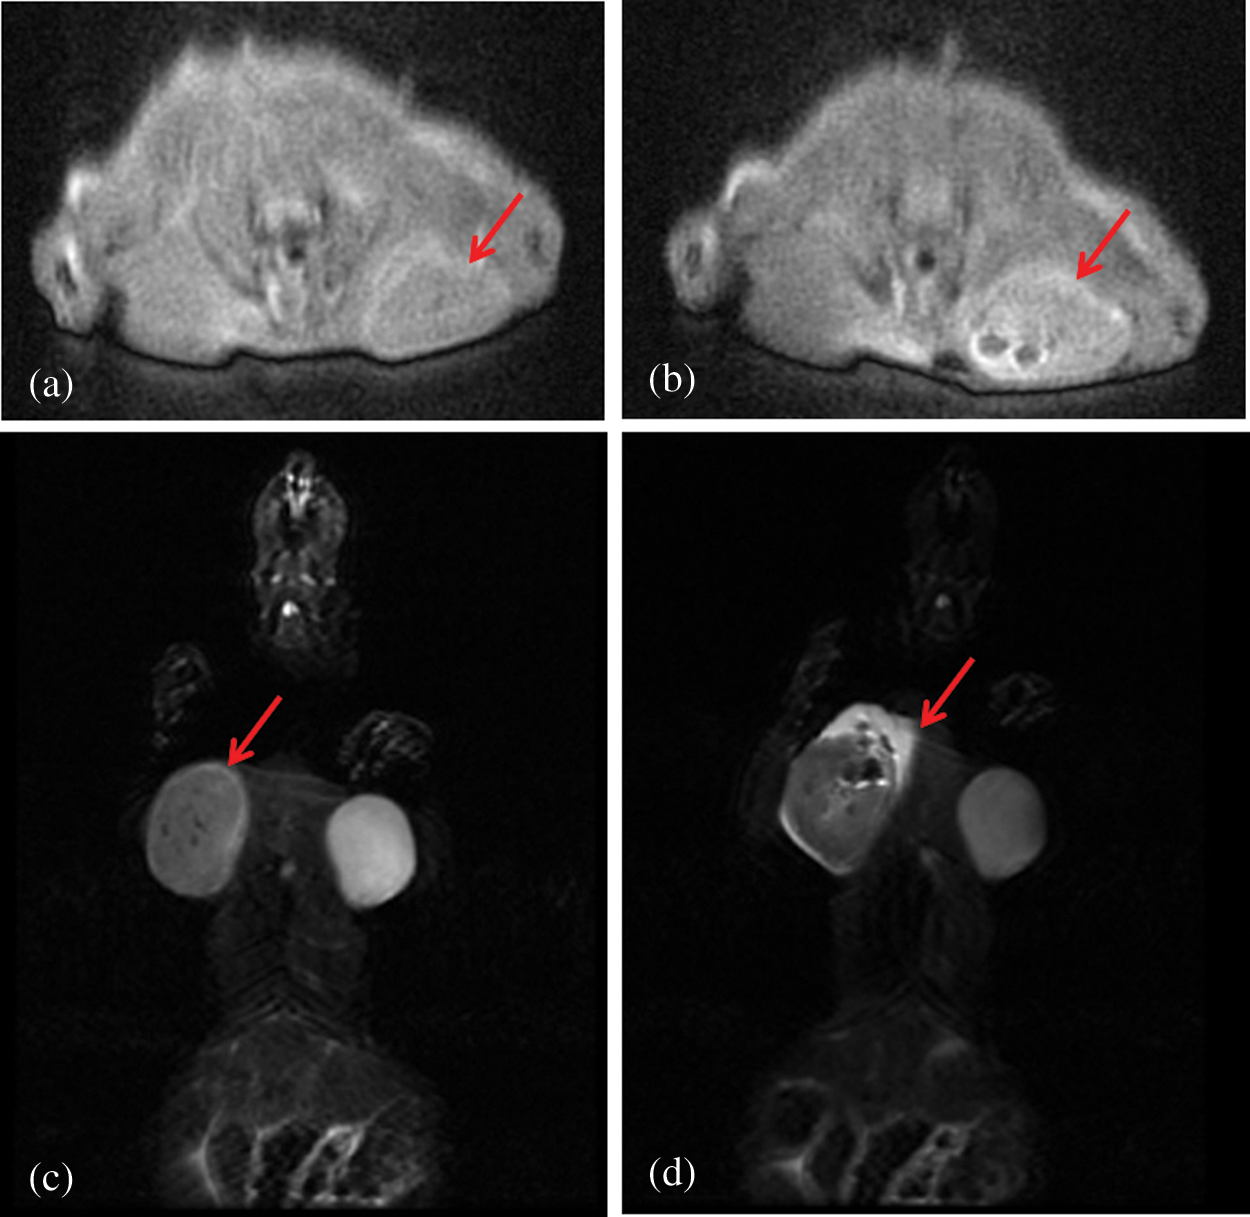

3.7 Magnetic Resonance Imaging in Vivo

Fig. 8 was the T2-weighted magnetic resonance images of subcutaneous tumors before and after administration of PFP/Lf-PLLA NBs. Signal intensity was determined in several regions of interest (ROI) and measured before and after injection of the contrast agent. Before the administration of PFP/Lf-PLLA NBs, MR scans were performed using T2-weighted spin echo sequences, and obtained images were used as pre-injection, as shown in Fig. 8a, the tumor exhibited obscure boundaries to surrounding tissues. After injection of nanobubbles, it was clear that the signal intensity within the tumor was significantly decreased and become a dark signal area that was distinct from the surrounding tissue. A negative enhancement effect was observed in the tumor. The magnetic resonance signal intensity in the tumor region significantly decreased by 47% in comparison to the image of the pre-injection. The hypointense region with the tumor lesion was indicative of nanobubbles accumulation, which caused a reduction in signal intensity on T2-weighted images. The decreased signal lasted for hours.

Figure 8: T2-weighted magnetic resonance images of the subcutaneous tumor pre- (a, c) and post-injection (b, d) of PFP/Lf-PLLA NBs. (a) and (b) are in the sagittal position,(c) and (d) are in the coronary position

The signal intensity (SI) in the tumor on T2-weighted magnetic resonance images was measured with a RadiAnt DICOM Viewer software by defining the ratio of the mean signal intensity (the five points) in the region of interest (ROI) within the tumor area to the signal intensity of the surrounding muscle. The smaller the value of ratio was, the more serious the signal attenuation was, and the clearer the boundary with the surrounding area was, which showed that the tumor area was the dark signal area. The SI (tumor/muscle) of pre-injection were 190.2 ± 2.566%, and the SI (tumor/muscle) of post-injection were 143.5 ± 9.660% (n = 5). The change of SI(tumor/muscle) was statistically significant before and after administration of PFP/Lf-PLLA NBs (P < 0.05). The results were shown in the following Fig. 9. These results indicated that PFP/Lf-PLLA NBs exhibited the ability to improve performance in magnetic resonance imaging and might be used in enhanced magnetic resonance imaging.